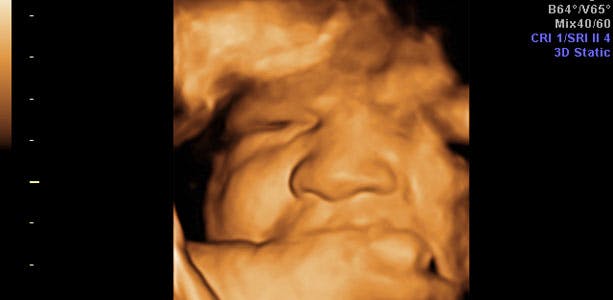

Gravid uge 40: Begynder at blive utålmodig

Navlesnoren er ved fødslen ofte så lang som baby selv. Moderkagen vejer ved fødslen cirka 1/5 til 1/6 af barnets vægt oftest 500 til 800 gram og er omkring to til tre centimeter tyk. Hvis man kigger på den side af moderkagen, som vender ind imod barnet, ligner navlesnoren stammen på et træ og blodårerne ligner grenene i trætoppen, og er unikke ligesom barnets fingeraftryk. I slutningen af ugen vejer barnet cirka 3600 gram.